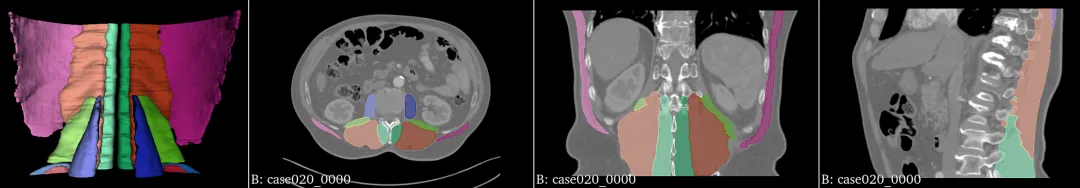

腹部肌肉分割: